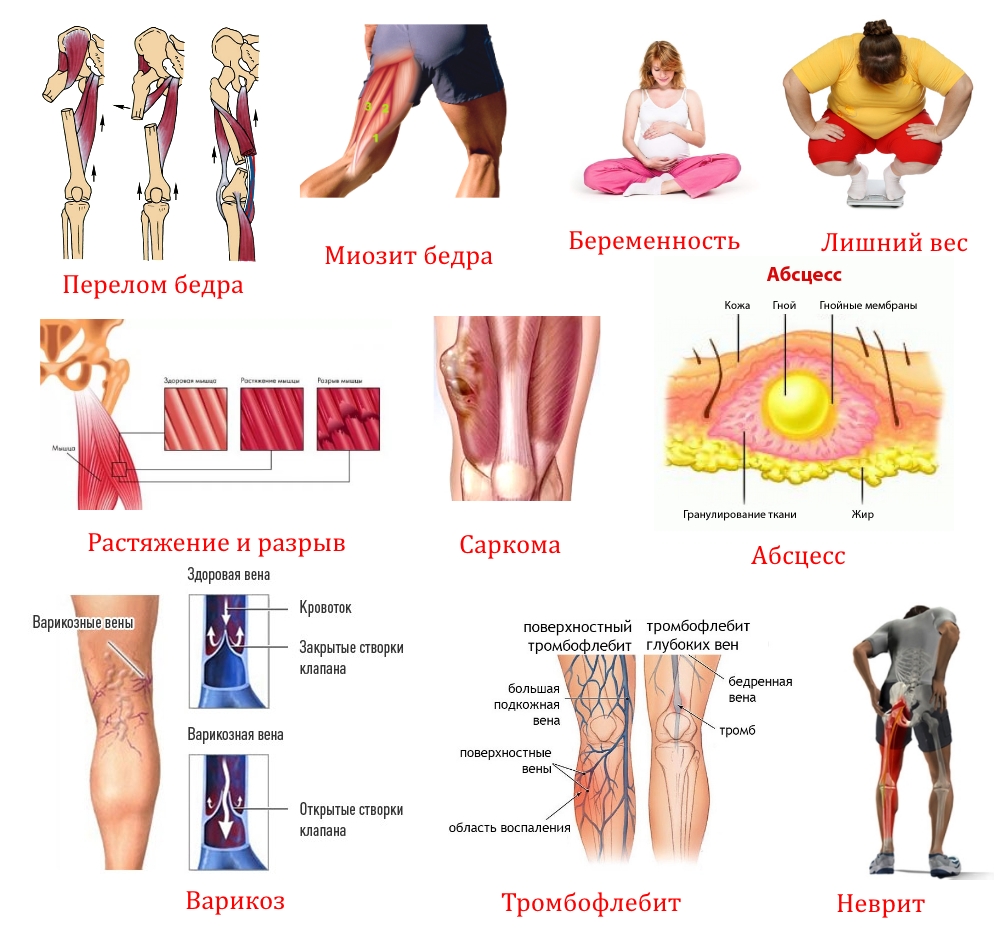

Возможные причины болей в ноге ниже колена и рекомендации